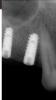

dantists Опубликовано 23 марта, 2008 Поделиться Опубликовано 23 марта, 2008 Два пациента, у одного три импланта у одного два. система oraltronics. одноэтапно синуслифт и установка имплантов. длина 10-12 мм. у двоих перед вторым этапом резорбция кости вокруг имплантов около 2 мм. почему? скину фото снимков. лоскут отслаивал практически с нёба. может ли быть от травмирования слизистой заглушкой во время жевания? Ссылка на комментарий

dantists Опубликовано 23 марта, 2008 Автор Поделиться Опубликовано 23 марта, 2008 мне кажется что это надо что-то другое попоробовать. язык всегда во вредные места лезет. хочет узелки пощупать,а там итак всё в натяжку. разве что капу защитную делать.вот другой пациент вот другой пациентподскажите в чём проблема. Ссылка на комментарий

Bier Опубликовано 23 марта, 2008 Поделиться Опубликовано 23 марта, 2008 на первом снимке - вы поставили имплантат в периодонт, отсюда и проблемы. На втором резьба у имплантатов не оголена, кстати на мой взгляд имплантаты в позициях 15-16 очень близко друг к другу. Есть ли там 3 мм? Ссылка на комментарий

dantists Опубликовано 23 марта, 2008 Автор Поделиться Опубликовано 23 марта, 2008 на первом снимке - вы поставили имплантат в периодонт, отсюда и проблемы. На втором резьба у имплантатов не оголена, кстати на мой взгляд имплантаты в позициях 15-16 очень близко друг к другу. Есть ли там 3 мм?но тут не в близкости дело,тут что-то другое. голову ломаю и ничего не приходит. сейчас кстати мировая тенденция 2мм. вот снимок как было на первом снимке - вы поставили имплантат в периодонт, отсюда и проблемы. На втором резьба у имплантатов не оголена, кстати на мой взгляд имплантаты в позициях 15-16 очень близко друг к другу. Есть ли там 3 мм?но тут не в близкости дело,тут что-то другое. голову ломаю и ничего не приходит. сейчас кстати мировая тенденция 2мм. вот снимок как было Ссылка на комментарий